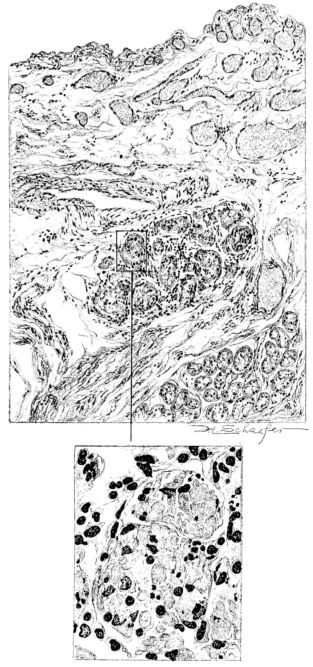

FIG. II. AUTOPSY NO. 98. DRAWING OF A SECTION THROUGH A TRACHEA SHOWING NECROTIZING HEMORRHAGIC INFLAMMATORY PROCESS OF THE MUCOSA.

The changes are less marked, perhaps, in the trachea than in its finer ramifications. The mucosa is constantly more or less destroyed and large areas, usually focal, are entirely devoid of their epithelial covering. This is replaced by a sparse exudate, composed largely of red blood cells, mucus, a small amount of fibrin, and nuclear fragments (Fig. II). It may dip into the submucosa for a short distance, but usually these indentures are associated with the ducts of the mucous glands into which the inflammatory reaction extends. A more striking feature than the exudate, however, is the edema and the congestion of the submucosa. The loose areolar tissue of the submucosa is spread widely apart, and throughout it distended blood vessels are very conspicuous. Occasionally such a vessel is broken and actual hemorrhage appears in the submucosa. Occasionally, too, the inflammation extends down the duct to the mucous gland itself, and here, also, aplastic inflammatory reaction is evident, inasmuch as the acini now stain intensely red with the cells undifferentiated from each other and specked here and there by broken remains of the dead nuclei (Fig. III). After the disease has continued for a short period, even at the end of five or six days, some regeneration of the epithelial lining may be seen (3) (Fig. IV). But despite this, the acute picture persists, and there goes on, side by side, an attempted repair characterized by epithelial regeneration and the same evidence of acute change. Since the lesion is essentially a superficial one, scars or contractures of any extent are not encountered in the trachea, even in examples of the disease that have ended fatally only after many weeks.[4]